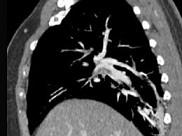

问题 男,56岁,食管癌术后,胸痛,呼吸困难,结合CT图像,最可能的诊断是 ( )

选项 A、肺水肿 B、肺不张 C、肺栓塞 D、支气管扩张 E、食管癌肺转移

答案 C